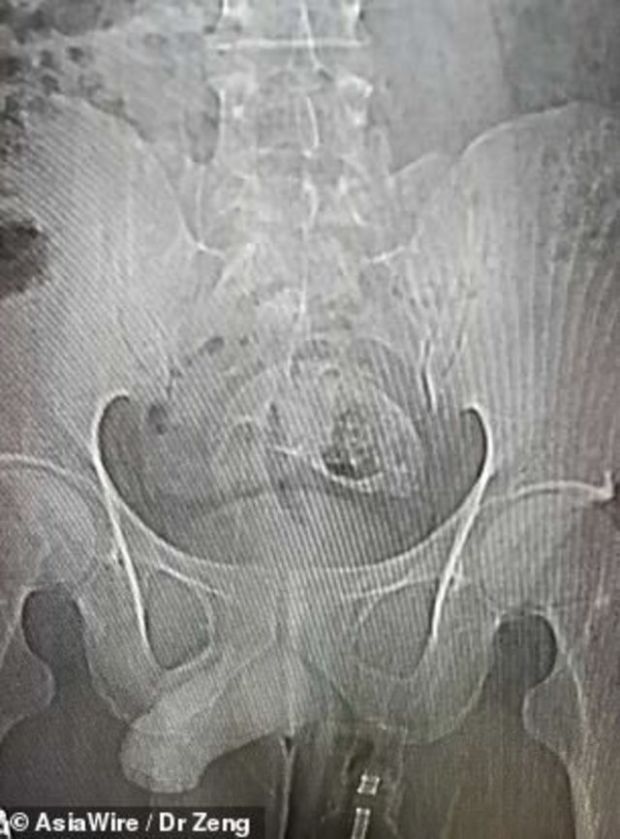

Çin’de karın ağrısı şikayetiyle hastaneye giden 30 yaşındaki bir kişinin rektumunda (bağırsak) balık tespit edildi. Balık, 5 saatlik operasyonla alınabildi.

Çekilen röntgende, adamın rektumunda (bağırsak) bir balığın olduğu görüldü.

Hastanede gerçekleştirilen 5 saatlik operasyonla balık adamın vücudundan çıkarıldı.